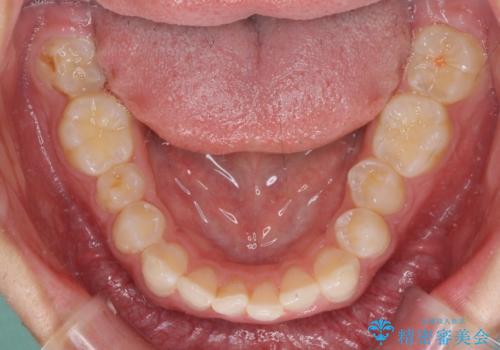

下顎前歯が全て隠れてしまうほどの深い咬合で、左右の奥歯は1歯対1歯で咬み合う状態でした。

前方に移動している上顎臼歯を補助装置にて遠心移動させることで1歯対2歯の臼歯咬合を目指し、同時に深い咬合を改善していくこととしました。

このような咬み合わせの場合、治療期間は2年以上がかかることが一般的で、3年程度かかることもありえるケースです。

強く深い咬み合わせにより下顎装置は頻繁に脱離するため、治療期間が長くなりますが、予定通りに終了させることができました。